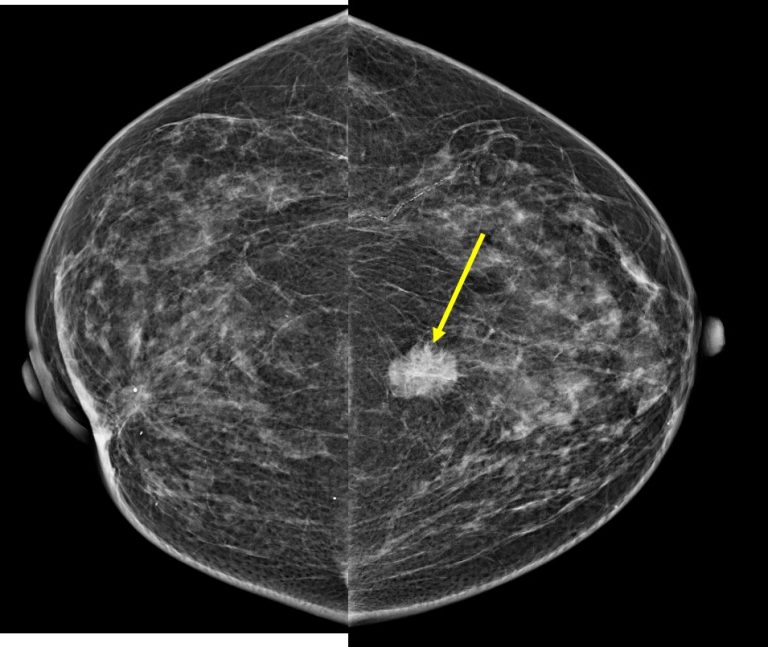

From www.researchgate.net

A mammogram of the left breast showed a left breast lesion with... Download Scientific Diagram Painful Breast Lump Radiology Most breast cancers don’t cause any pain, even if they first appear as a lump or a bump. Palpable breast masses may present in various circumstances: Breast lumps are common and cause significant emotional stress for the patient when detected. Most palpable breast lumps are benign. For women 40 years old. Do breast cancer lumps ever hurt? In almost all. Painful Breast Lump Radiology.